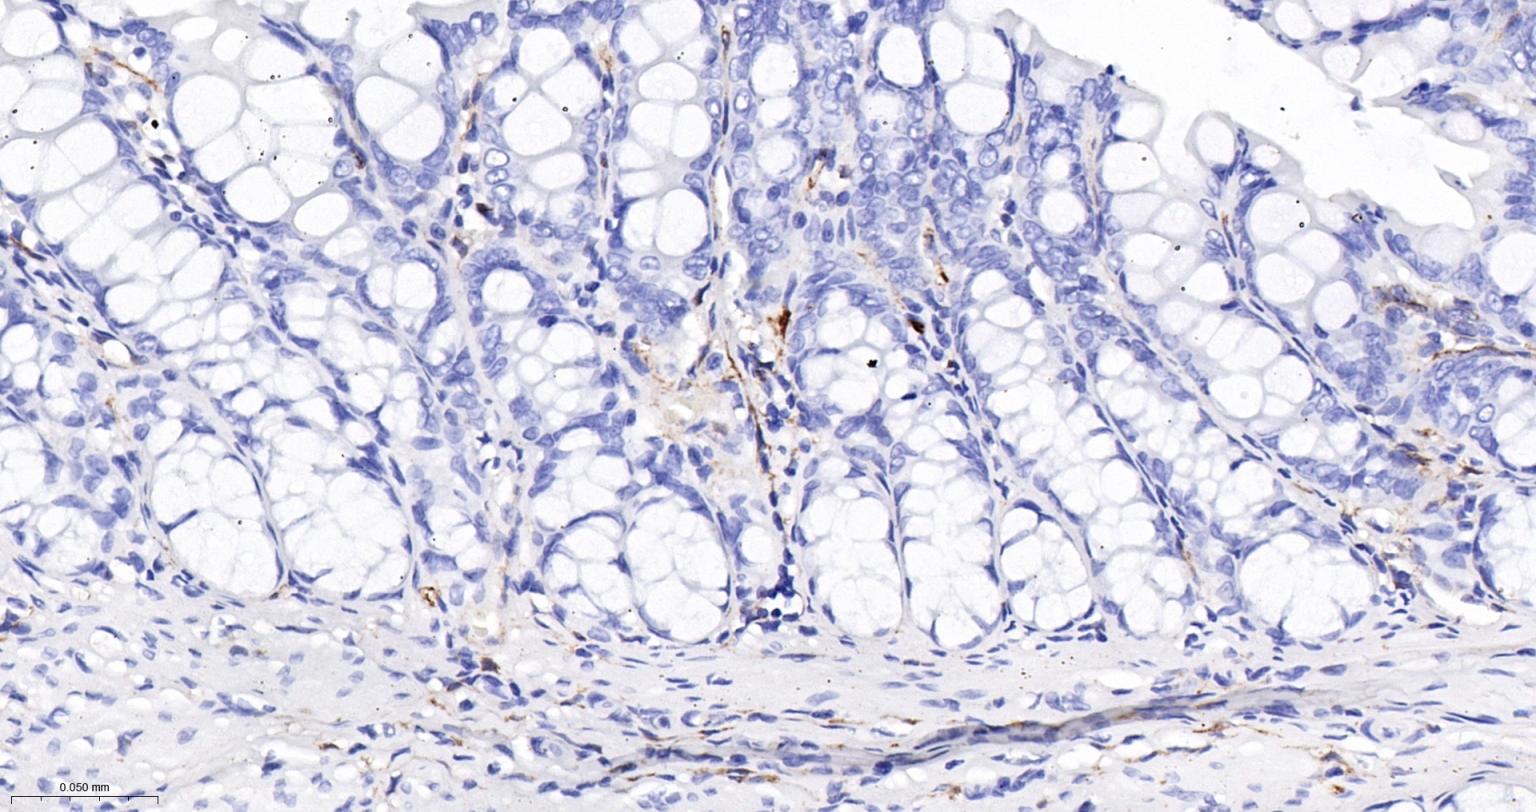

Paraformaldehyde-fixed, paraffin embedded Human Colon; Antigen retrieval by boiling in sodium citrate buffer (pH6.0) for 15 min; The section was incubated with FSCN1 Monoclonal Antibody, Unconjugated (bsm-61626R) at 1:200 overnight at 4°C, followed by conjugation to the bs-0295G-HRP and DAB (C-0010) staining.

Paraformaldehyde-fixed, paraffin embedded Rat Colon; Antigen retrieval by boiling in sodium citrate buffer (pH6.0) for 15 min; The section was incubated with FSCN1 Monoclonal Antibody, Unconjugated (bsm-61626R) at 1:200 overnight at 4°C, followed by conjugation to the bs-0295G-HRP and DAB (C-0010) staining.

Paraformaldehyde-fixed, paraffin embedded Mouse Colon; Antigen retrieval by boiling in sodium citrate buffer (pH6.0) for 15 min; The section was incubated with FSCN1 Monoclonal Antibody, Unconjugated (bsm-61626R) at 1:200 overnight at 4°C, followed by conjugation to the bs-0295G-HRP and DAB (C-0010) staining.